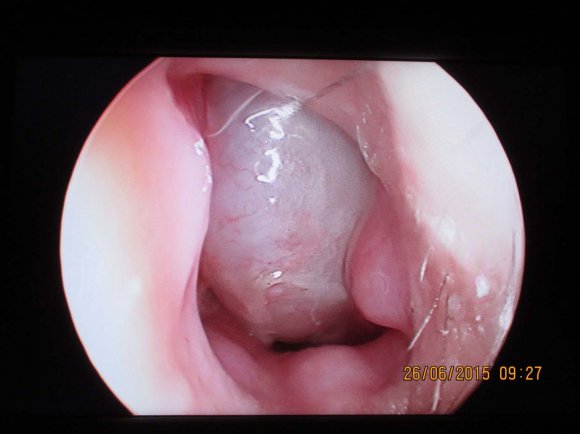

Clinical example ? 2. Patient S., 28, arrived for treatment in emergency procedure. He had a traumatic fracture of the right zygomatic complex with displacement. He addressed doctors 5 days after the injury.

At CT 3D determined violations of integrity skull bone clastic complex of the right zygomatic complex near the body of the ZC, the lower edge of the orbit and ZAC with the offset (Fig. 5). After 6 months of the operation as a result of the MSCT control consolidation of the fracture was detected in all the loci where the bone fragments were in contact during osteosynthesis. In the ZAC area a bone defect remained that was restored with a bone titanium plate (Fig. 8).